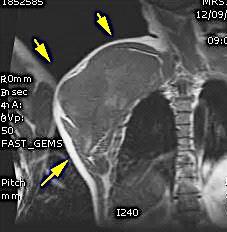

Tumor desmoide (“Fibromatosis agresiva”)

T1: Isointensos con músculos.

T2: Señal intermedia y de alta intensidad.

Presencia frecuente de áreas curvilíneas y lineales dentro de la lesión

Mansour J et al. Diagnostic and Imaging Approaches to Chest Wall Lesions. Radiographics 2022